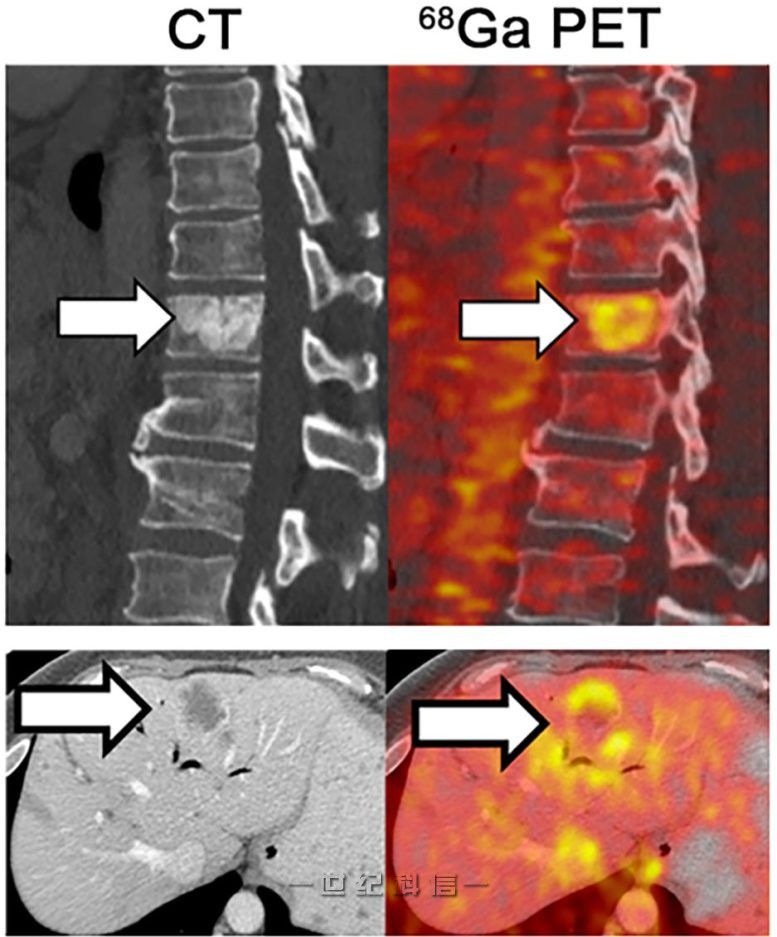

PET 成像(右)显示在胰腺导管腺癌患者的脊柱和肝脏中生长的转移性肿瘤中铁的积累。图片来源:© 2022 蒋等人。最初发表在《实验医学杂志》上。https://doi.org/10.1084/jem.20210739